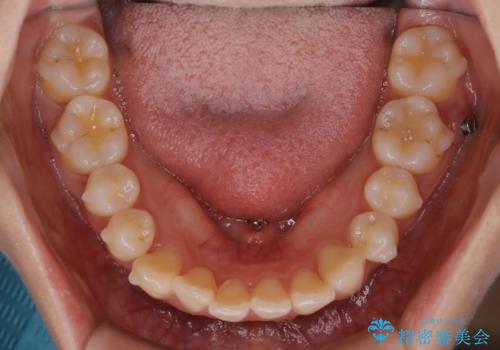

- 前歯のガタつきと噛み合わせの改善を主訴に初診来院され、審査の結果マウスピース装置による非抜歯での矯正を行うこととなりました。

元々の顎骨や口腔・歯槽骨が小さく、どうしても歯が並びきらない状況になっていました。マイクロインプラントという固定源からゴムかけを行うなど、補助装置を活用しながら臼歯部を順番に遠心方向(奥)に移動させていくことで抜歯をしなくても歯が並ぶよう計画を立てました。

歯のガタつきを治すため矯正治療を希望。審査の結果、非抜歯での矯正が可能であるという見通しが立ったためインビザラインによる非抜歯矯正治療を行った。

歯を並べるスペースを作るために、歯の遠心移動と歯列の拡大、歯自体を少しだけ小さく削る(IPR)という方法を複合的に組み合わせて配列を行いました。遠心移動用のゴムかけにはマイクロインプラントという小さいネジを用いて骨に直接固定源を求めました。